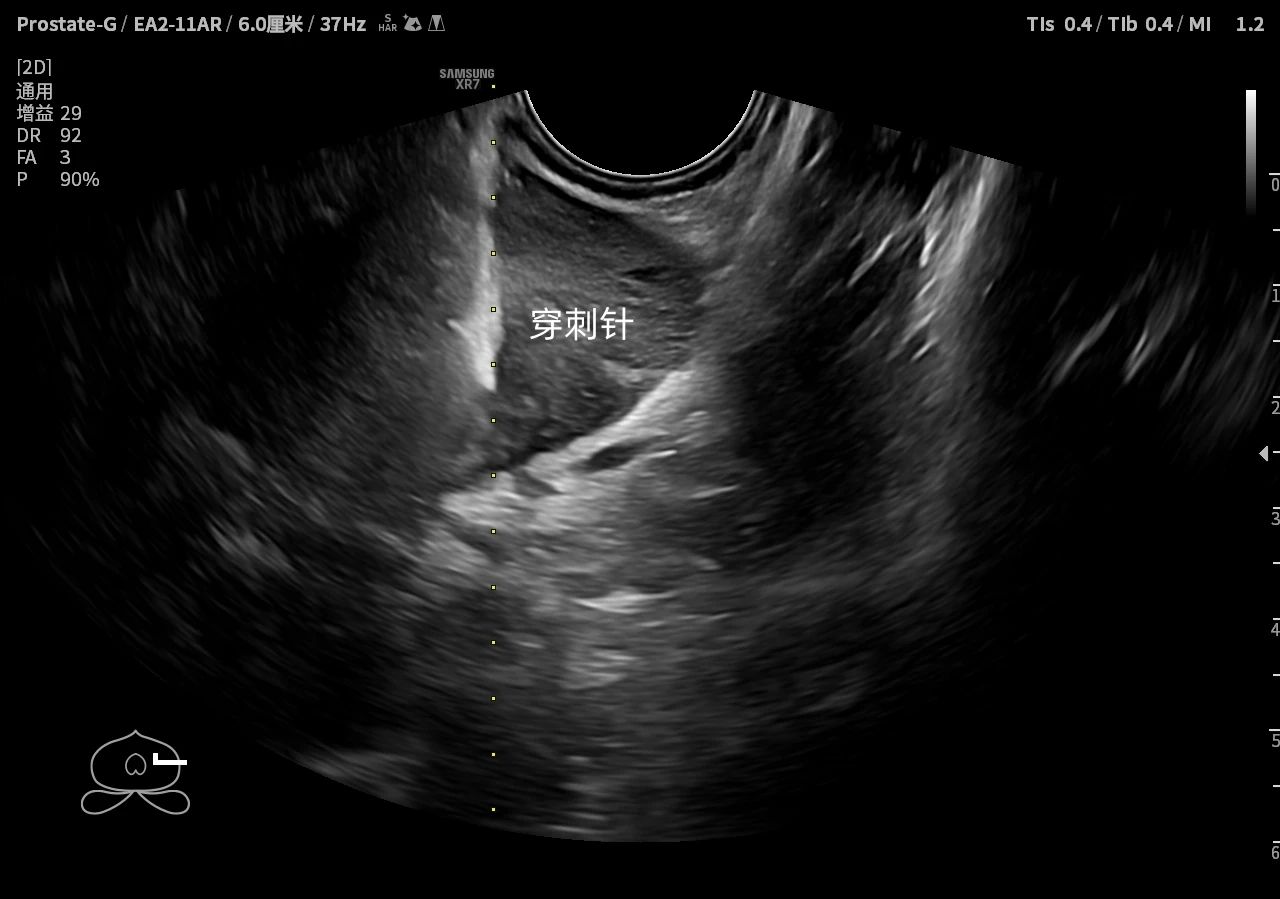

后在医生的建议下,沈先生接受了经直肠彩超及超声造影下行前列腺穿刺检查,病理结果显示为(前列腺-前列腺右侧叶6)前列腺腺泡腺癌,Gleason分级8分,ISUP分级分组4级。“就像打针一样,没什么痛苦,术后仅留有了一个针眼大小创口。”沈先生回忆道。

据了解,我院泌尿外科与超声科携手开展前列腺专科建设合作,融合3.0T磁共振与超声造影,开展超声实时引导下的前列腺敏感部位精准定位穿刺技术,阳性检出率明显提高,是早期确诊前列腺恶性肿瘤的金标准。